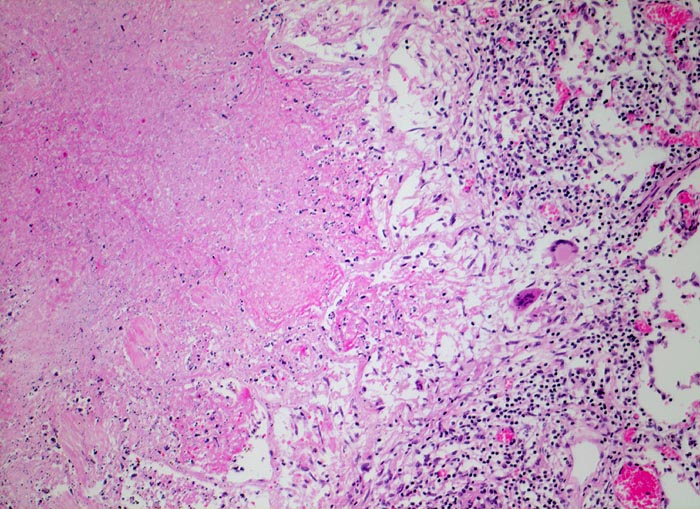

Lungentuberkulose: verkäsendes Granulom

Granulom mit zentraler verkäsender Nekrose gefolgt von einem Epitheloidzellwall mit Riesenzellen vom Langhanstyp und einem äusseren Saum von Lymphozyten.

Autoptisch wird ein akuter Myokardinfarkt der Vorderwand diagnostiziert. In beiden Lungen fallen oberlappenbetonte knotige weisse, teils kleeblattartige Infiltrate auf und eine subapikal gelegene kleine Kaverne. Einzelne hiläre Lymphknoten der rechten Seite weisen Verkalkungen auf und bilden zusammen mit einem subpleural im Mittellappen gelegenen verkalkten Herd den abgeheilten Primärkomplex. In den käsigen Nekrosen können vereinzelte säurefeste Stäbchen nachgewiesen werden.